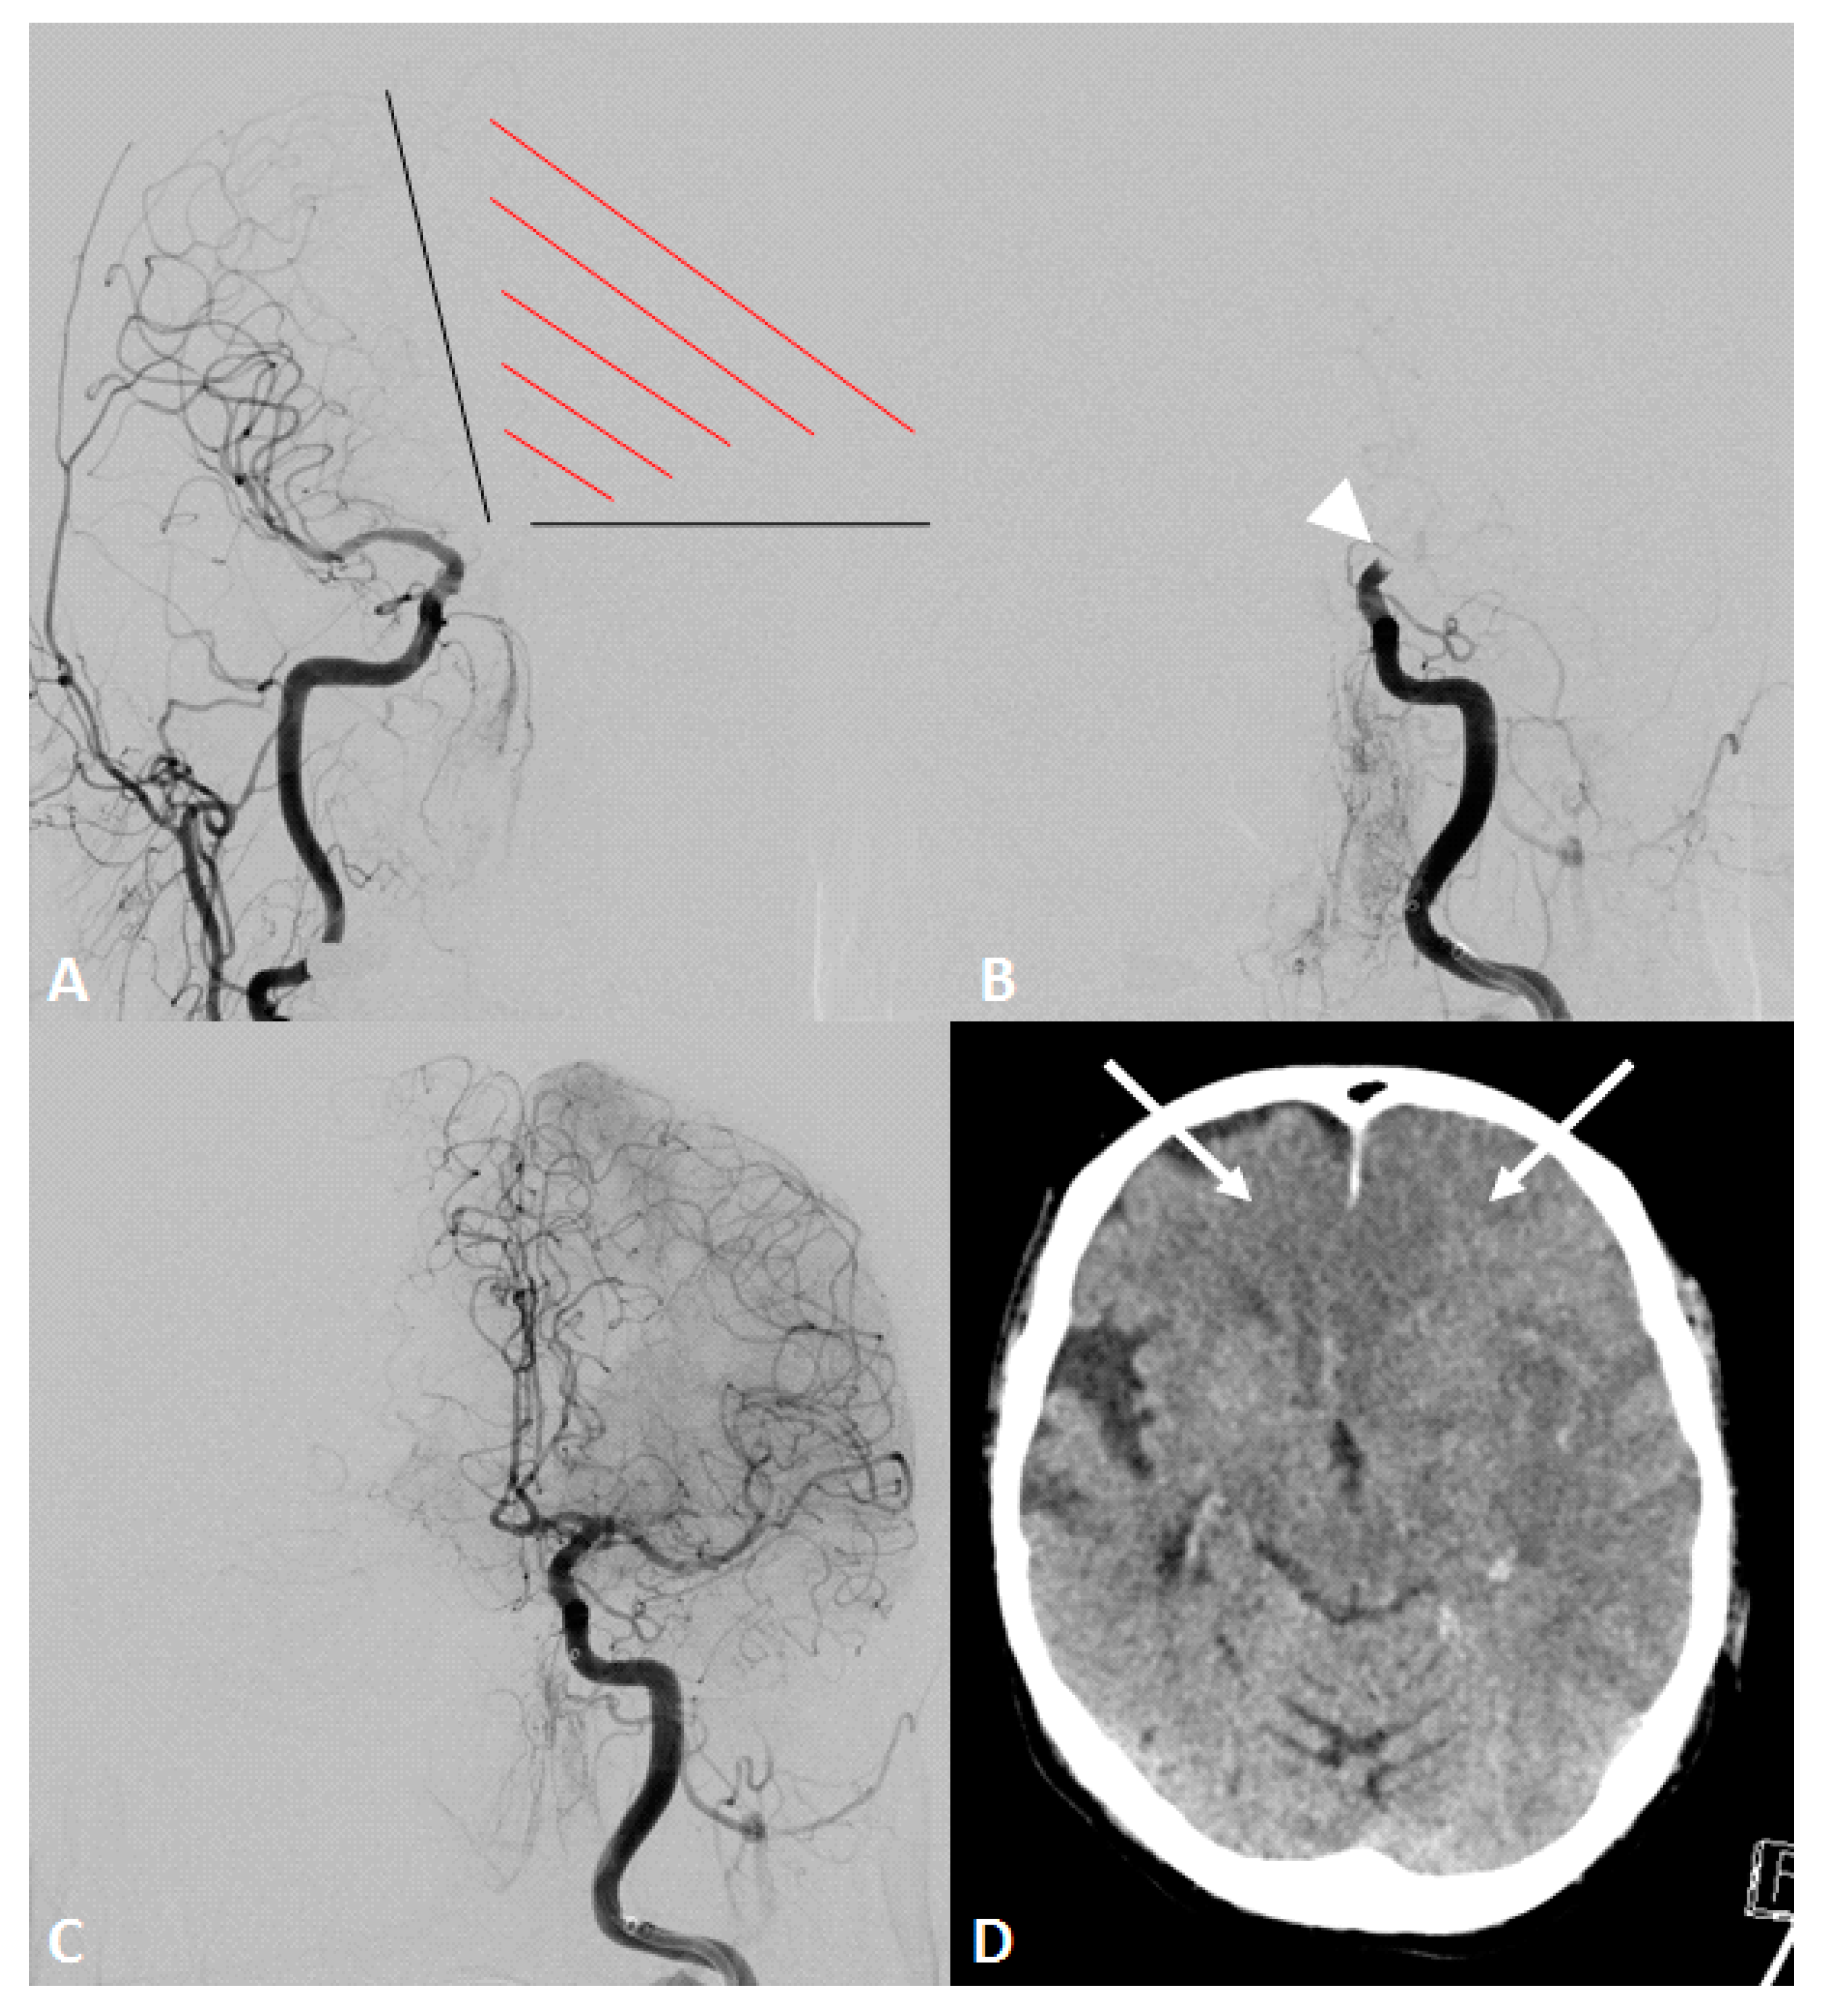

Evaluation of cerebral vasculature was obtained either from digital subtraction angiography (DSA) or from baseline imaging (including computed tomography angiography, CTA, or magnetic resonance imaging angiography, MRA). Primarily, the caliber of the contralateral A1 segment was evaluated on DSA if the vessel was depicted during the endovascular procedure, e.g., through contralateral ICA injection prior to MT to evaluate collateral supply (Figure 1) or on final angiogram through (retrograde) blood flow via AcomA. The absence of the A1 segment was defined as ‘aplasia’. If the vessel diameter of the contralateral A1 segment was reduced >50% in comparison to the ipsilateral site, it was graded as ‘hypoplasia’. Both terms together were defined as ‘functional aplasia’.

Figure 1.

An octogenarian patient presented with an acute onset of right-sided hemiplegia and disturbed consciousness. Initial computed tomography showed an occlusion of the distal internal carotid artery (ICA) on the left side and no detectable infarction (not shown). Intravenous thrombolysis was initiated, and the patient was immediately transferred to the angio suite. (A) Initial angiogram of the contralateral ICA demonstrated an aplasia of the a1 segment and missing collaterals to the affected hemisphere, including both anterior cerebral artery (ACA) territories (red shaded area). (B) Angiogram of the left ICA showing distal ICA occlusion (white arrowhead). (C) Final angiogram after mechanical thrombectomy using two maneuvers with stent-retrieving showed a successful recanalization of the ICA with complete reperfusion of the middle cerebral artery (MCA) and both ACA territories. (D) Computed tomography on the next day demonstrated an expanded cerebral infarction in MCA (Alberta stroke programme early CT score of 0) and both ACA territories (white arrows). The patient died on the same day.